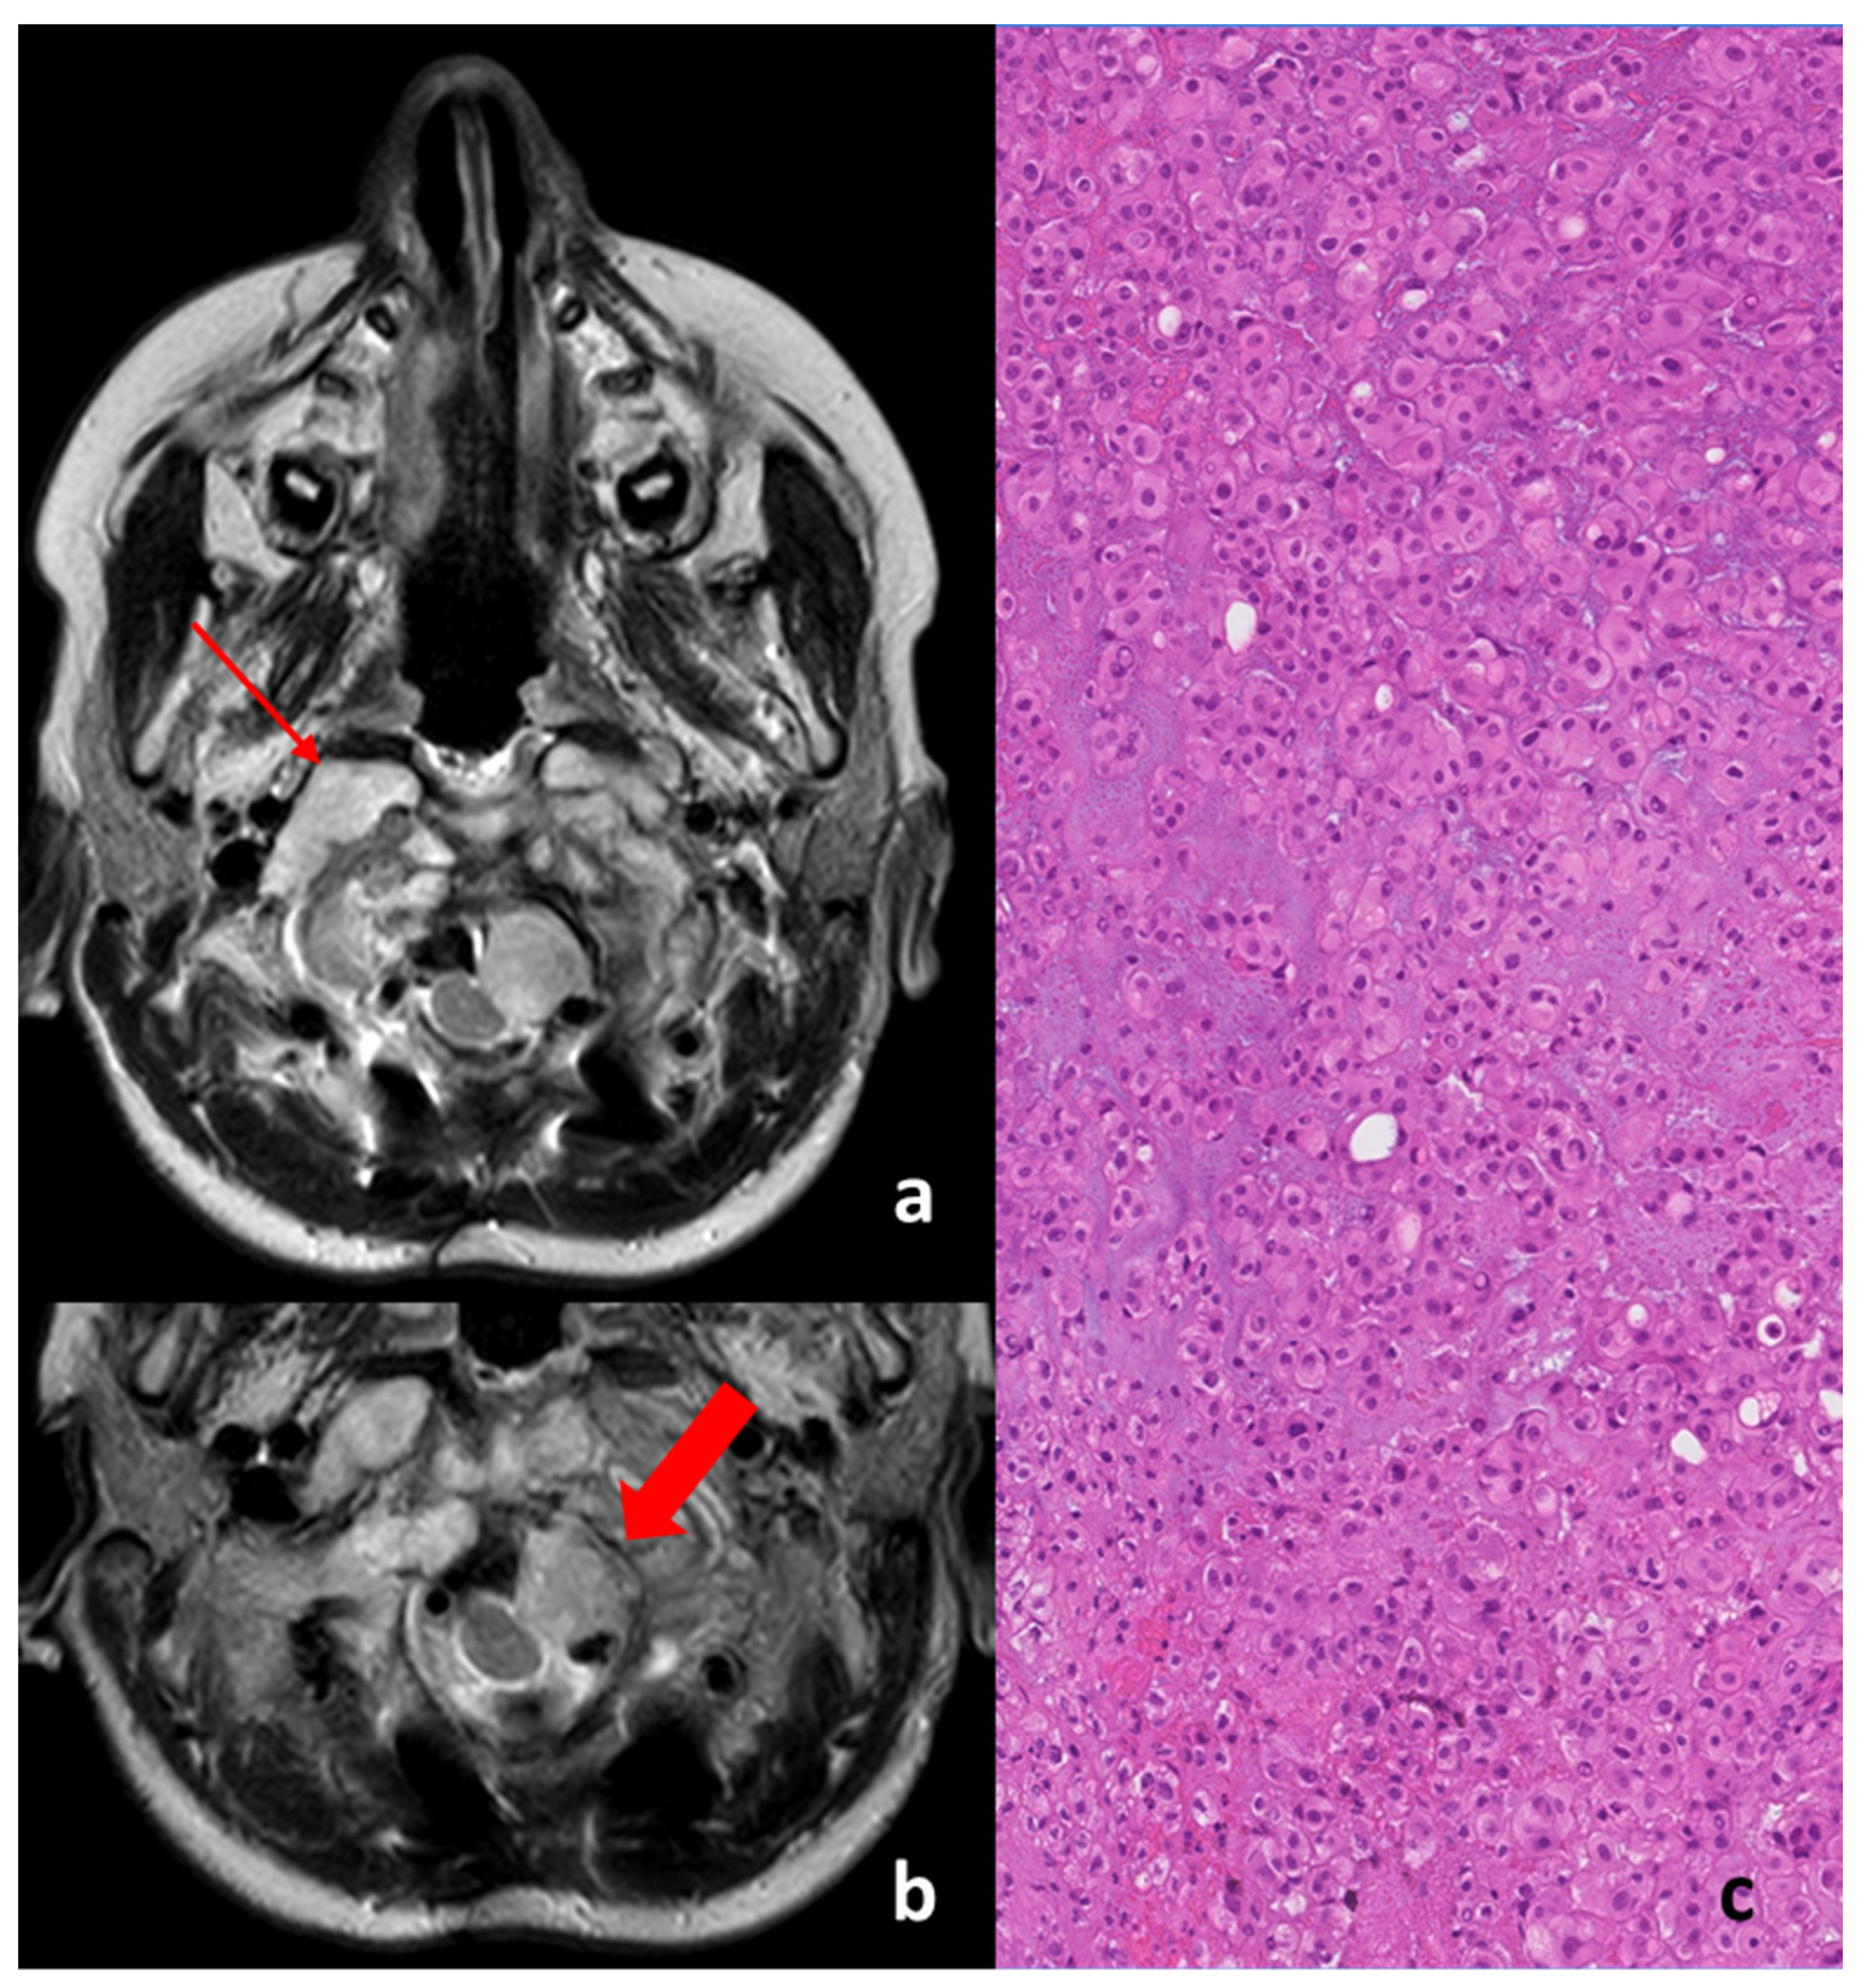

Figure 2 “a” and “b” show the axial T2-weighted MRI with the macroscopic residual of the disease post-surgery, just before the beginning of proton therapy treatment.

As can be seen in the top image, the disease was present bilaterally on the tooth of the axis and was characterized by two different MRI-signaled components in T2, with one component being frankly hyperintense in T2, typical of the radiological signal of the classic histology upon the right condyle (thin red arrow in Figure 2a,c).

One nodule component was non-homogenous hypo–hyperintense in T2 and was represented by a left para-medullary bulb with compression and a shift on the spinal cord (thick red arrow in the Figure 2b); such a feature is less common in the classic type of histology but is more typically present in de-differentiated chordomas (it is possible that it can appear in post-surgical resection) [7,8]. The histological picture is of a neoplasm composed by chords and strands of tumor cells embedded in a myxoid background. The tumor cells show abundant pink cytoplasm and round regular nuclei with little cytological atypia. Some cells show multiple cytoplasmic vacuoles creating the classic bubbly appearance of physaliferous cells. On immunohistochemical examination, the neoplasm appears diffusely immunoreactive for cytokeratin and EMA and shows nuclear immunoreactivity for brachyury and variable S100 positivity. A diagnosis of conventional chordoma was made.

Figure 2. Pre-proton therapy images (representative T2-weighted MRI axial views (a) and (b)) and histologic examination after biopsy at the first diagnosis (c).